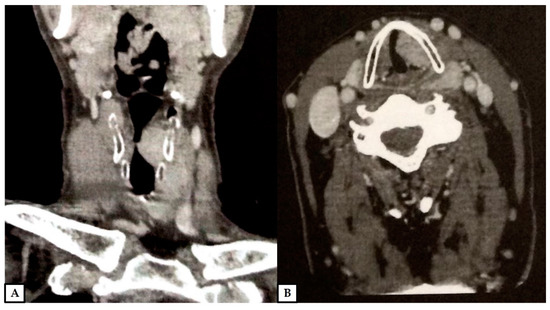

Figure 1. A 66-year-old man presented with a previous diagnosis of granular cell tumor of the left vocal cord on an incisional biopsy performed at another hospital. Contrast-enhanced computed tomography revealed a soft tissue mass of 2.8 × 2.5 × 1.1 cm of the left vocal cord, with transglottic extension, spreading to the supraglottis, subglottis, paraglottic space and the anterior commissure, causing partial obstruction of the laryngeal lumen; no infiltration of the cartilage was evident (computed tomography scans; (A): coronal plane, (B): axial plane; previously unpublished, original photos).